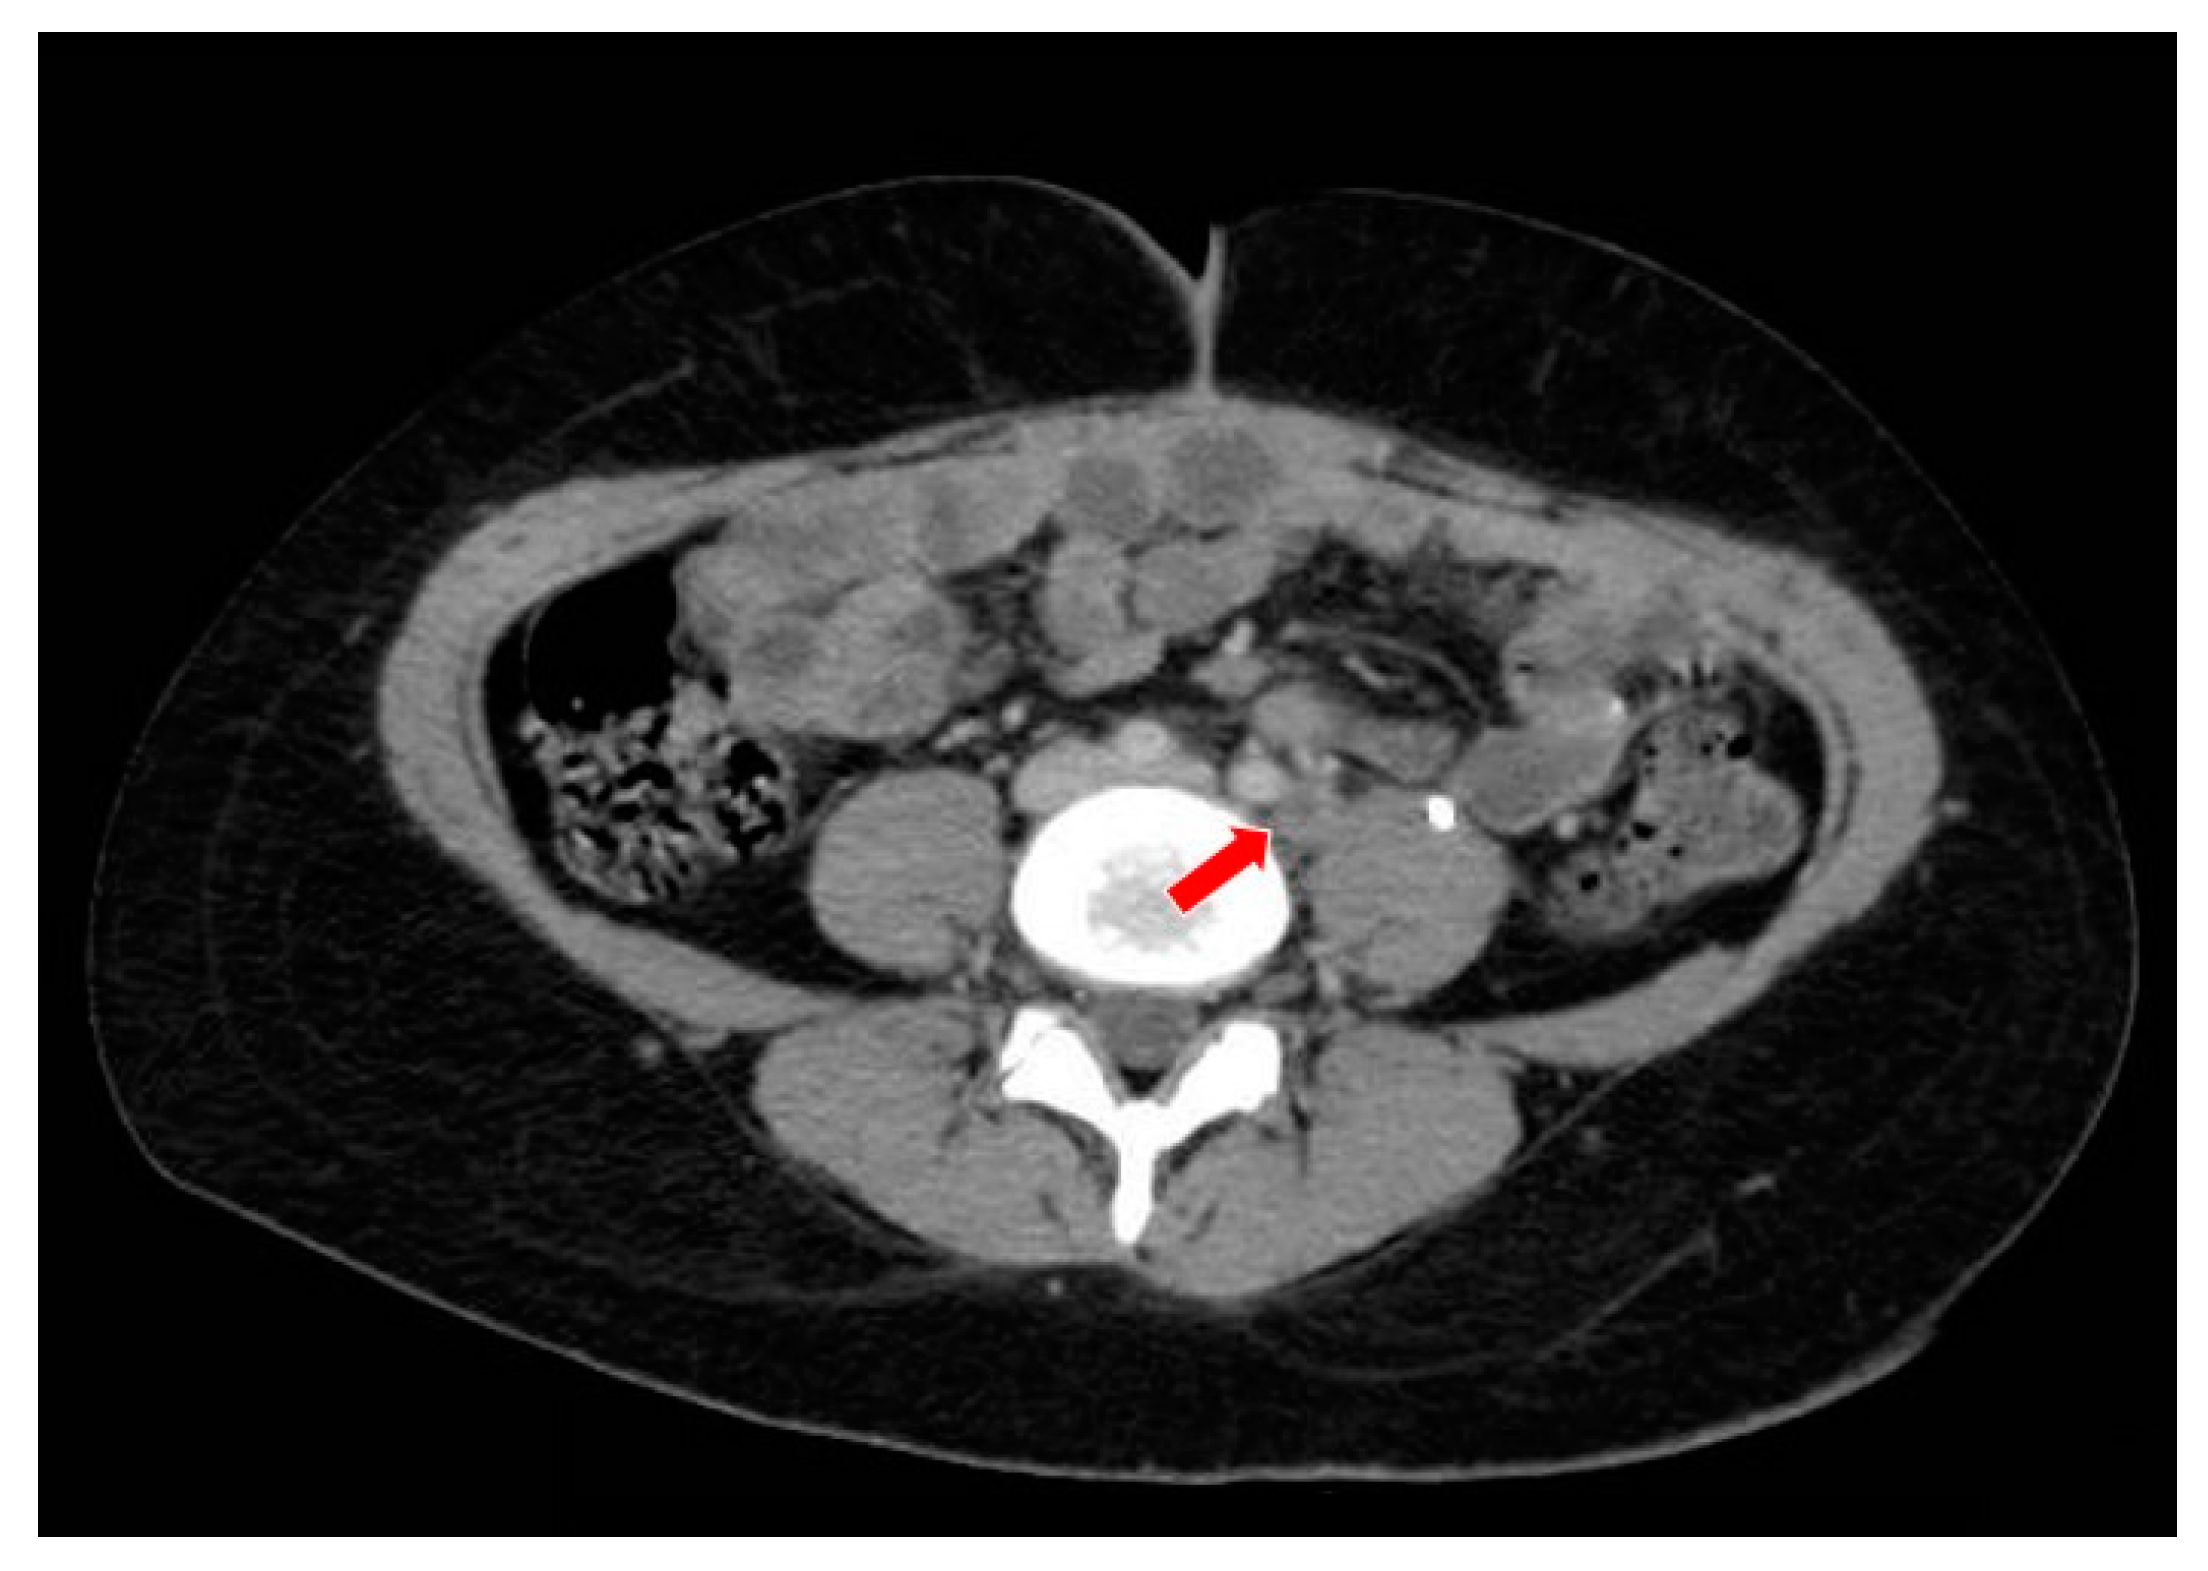

Figure 7.

The computed tomography study in the portal phase showing a lymph node in the left iliac chain with a rounded aspect and a necrotic center (red arrow), suggestive of secondary neoplastic involvement (relapse).